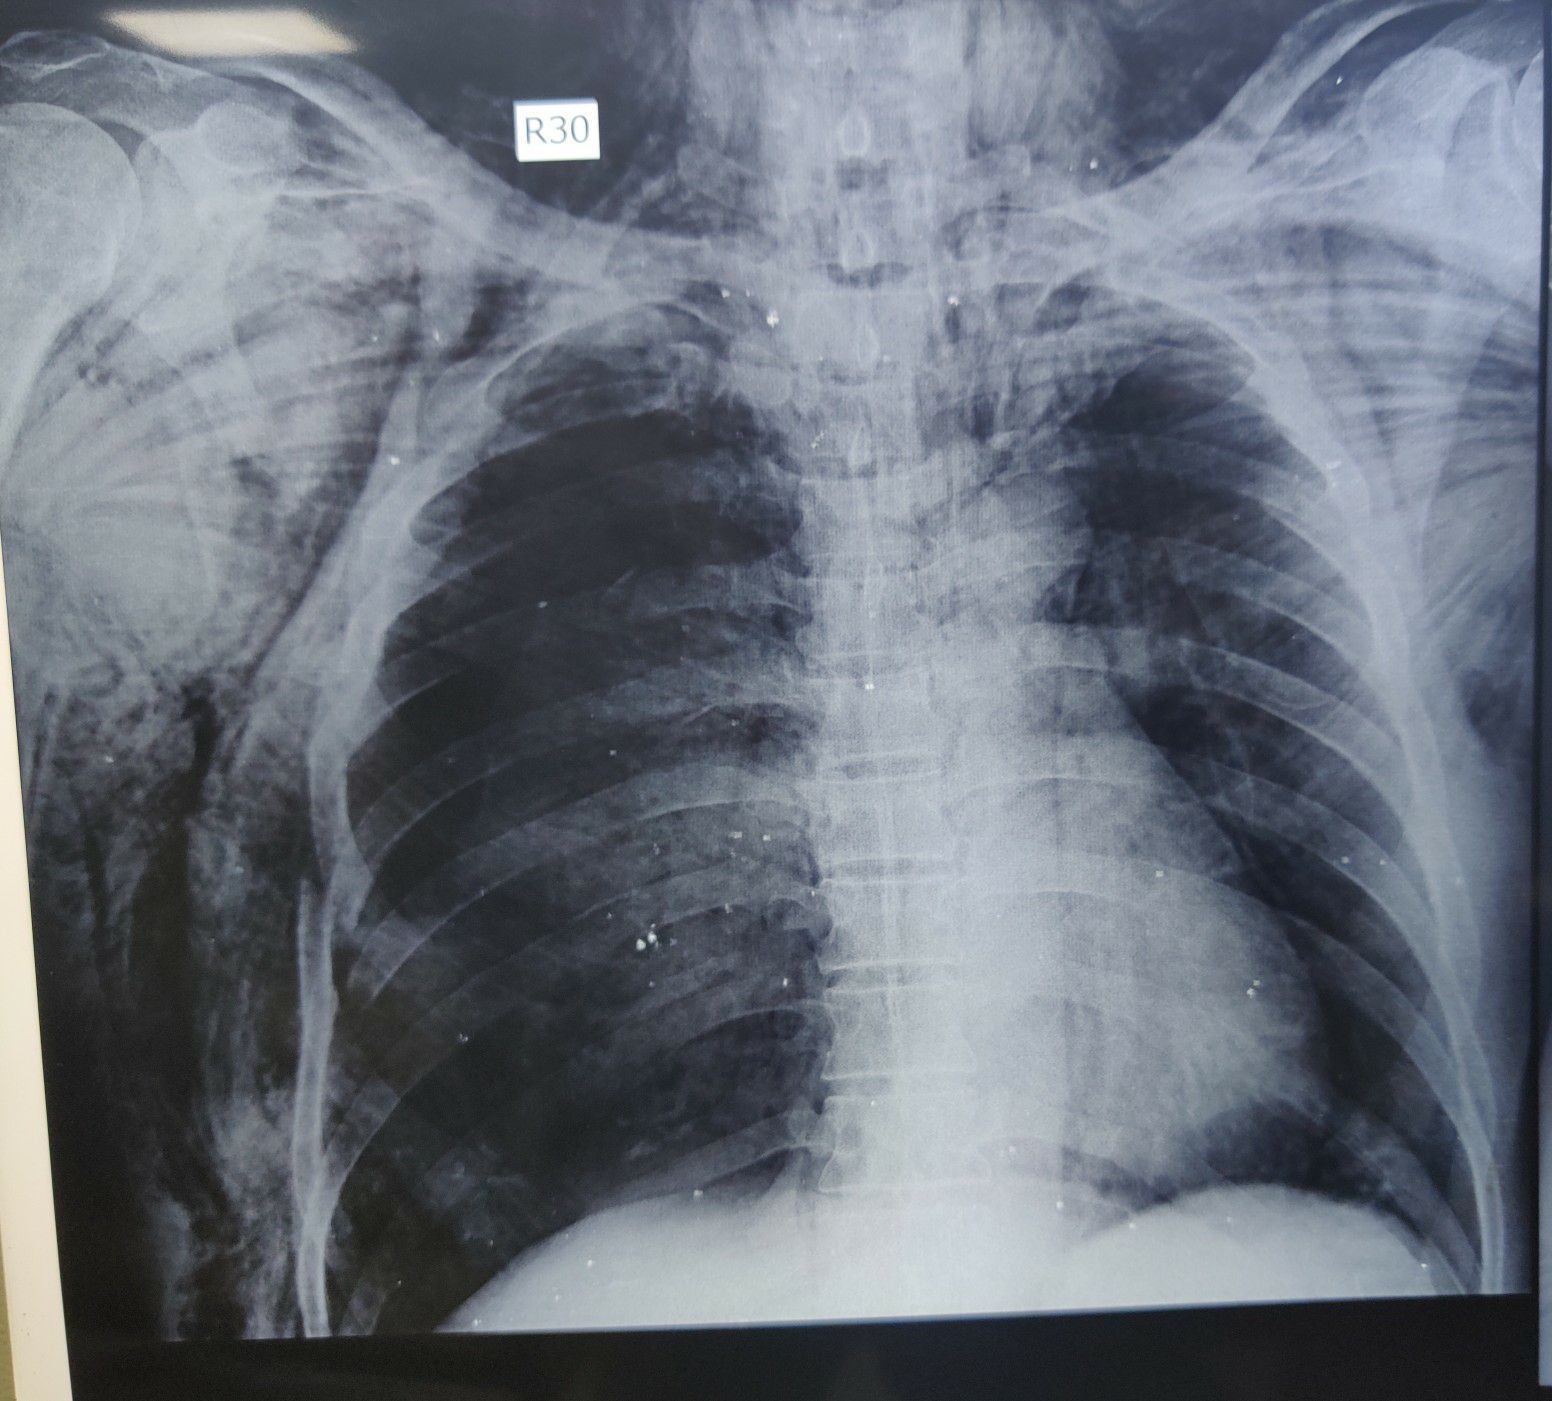

Subcutaneous Emphysema

5th and 6th Rib Fracture

Emergency

Rta

Ribs